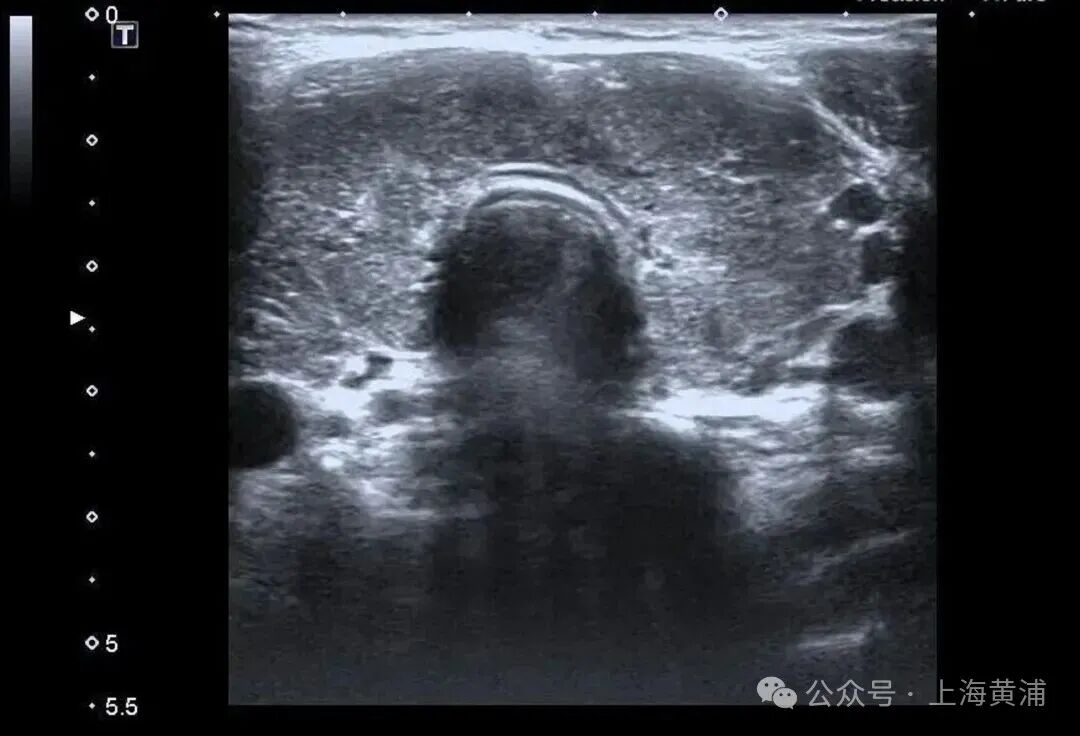

入院后的检查结果显示

陈女士的身体

正被一场“激素风暴”席卷

甲状腺功能检查中,游离T3高达20.83pmol/L(正常值3.5-6.5pmol/L),游离T4高达88.42pmol/L(正常值11.5-22.7pmol/L),这两项核心激素都超过正常上限数倍,而本应调控它们的促甲状腺激素(TSH)却几乎测不出来,这明确证实了陈女士患有极其严重的甲状腺毒症。心脏超声结果同样不容乐观,射血分数仅有40%(正常应高于55%),这意味着心脏泵血能力大幅下降。

同时,CT检查发现她的双侧胸腔、腹腔存在积液。综合各项检查结果,医生判断陈女士患上了甲状腺危象,这是甲亢最凶险的并发症。